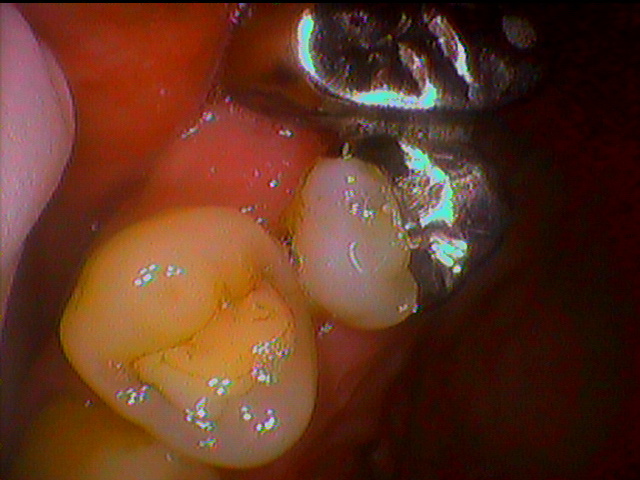

本日は以前に親知らずが痛くなり抜歯をした患者さんの術後のチェックを行いました。

痛みが出た親知らずがかなりの深さの虫歯になっておりました。消炎処置というレヴェルでは痛みが引かず、抜歯の説明をさせて頂きました。

抜歯後約1週間でこのような良い状態まで回復されていましたのでとても良かったです。